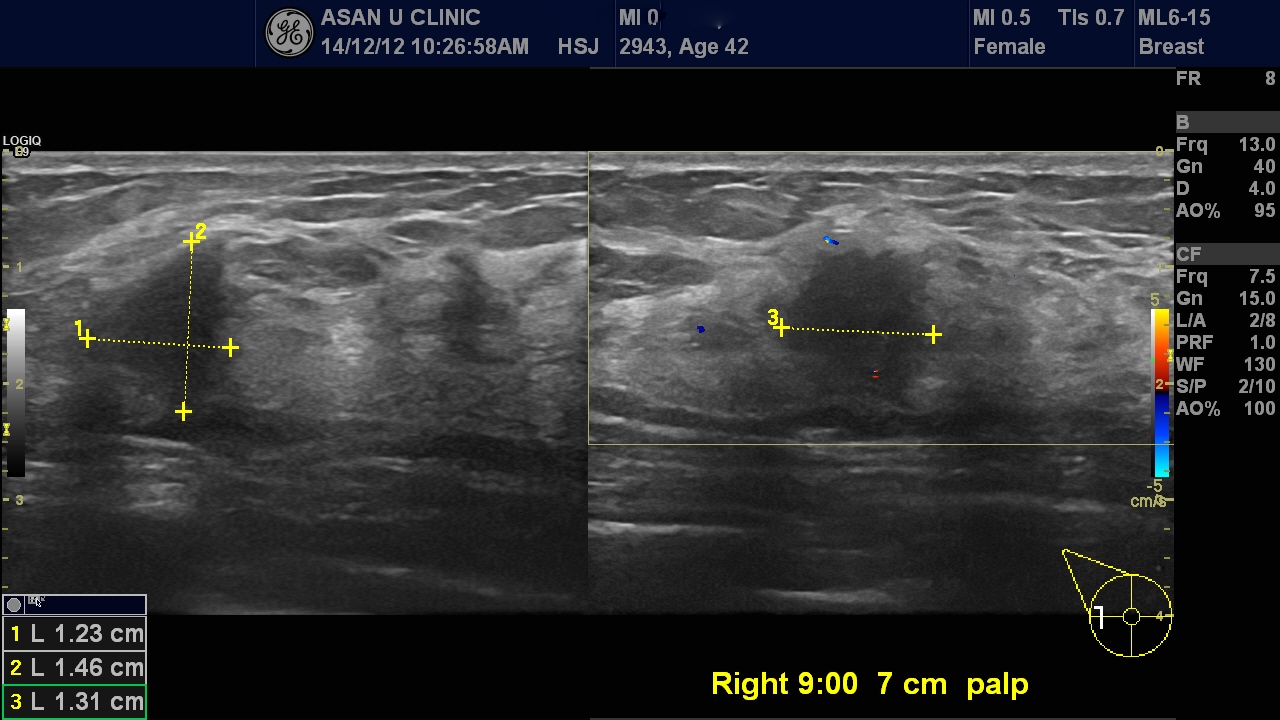

본원 초음파상 만져지는 부위에 1.4cm의 혹과 주위에 몇몇 위성처럼 떨어져있는 0.5cm전후의

혹들도 있어 다발성 유방암이 의심되 보였습니다.

조직검사를 시행하여 침윤성 유관암 진단되었습니다.